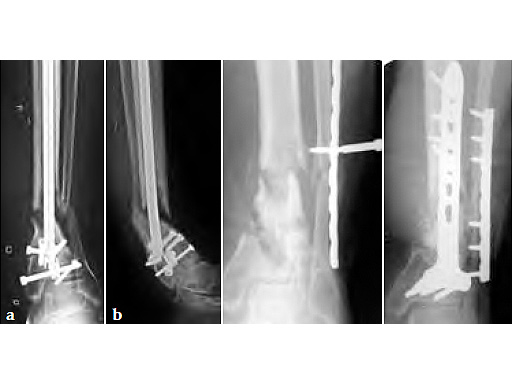

31-year-old male with a 2.5-year history of a distal tibial nonunion/malunion with three previous surgeries. Significantly compromised soft-tissue envelope anteriorly.

Removal of the intramedullary nail followed by posterior iliac bone grafting and plate fixation of both the fibula and tibia. A posterolateral approach was used to approach both the tibia and the fibula. The posterior locking T-plate was used for fixation of the tibia.

Some residual varus deformity of the tibia remains, but clinically the patient is full weight bearing and has returned to work after 4.5 months.